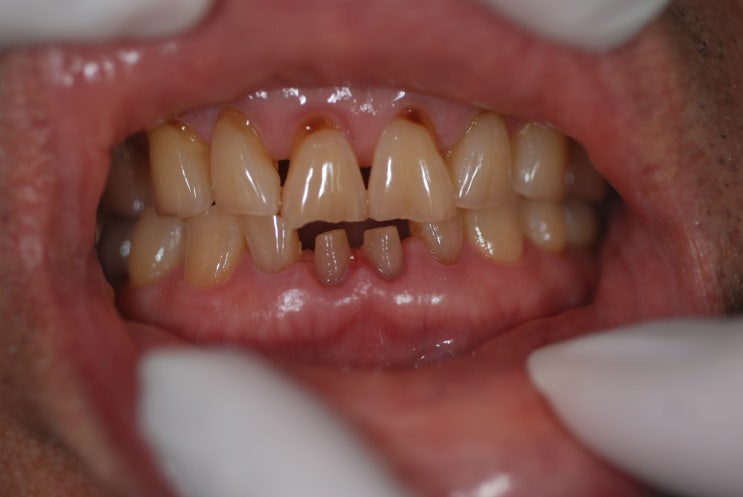

[일원동 치과] 하악 전치부 심한 마모 지르코니아 크라운

안녕하세요 수서역치과 수서신혼희망타운 치과 수서서울삼성치과 원장 이재현입니다 오늘은 좀 특이한 케이...